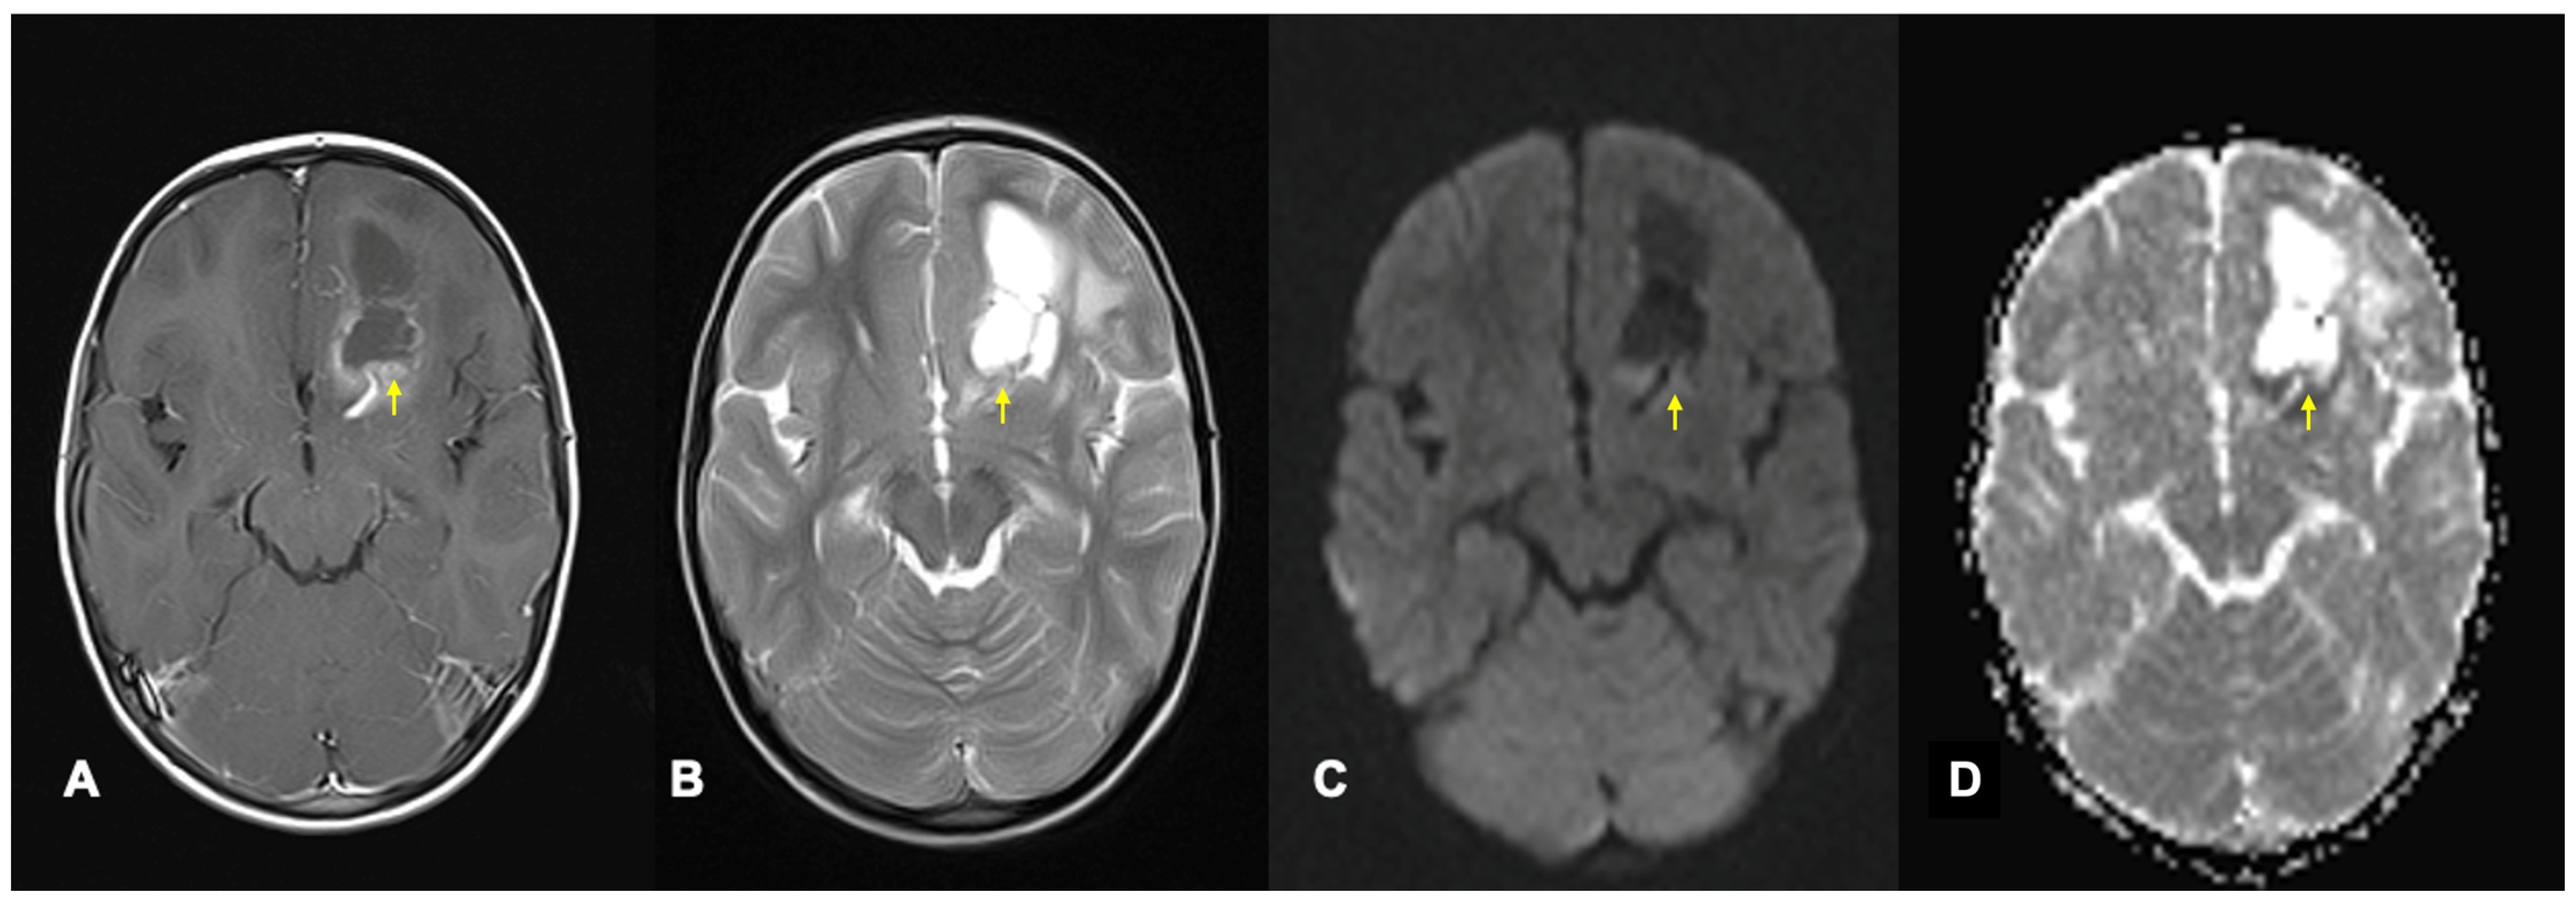

- Miller, N.G.; Reddick, W.E.; Kocak, M.; Glass, J.O.; Löbel, U.; Morris, B.; Gajjar, A.; Patay, Z. Cerebellocerebral diaschisis is the likely mechanism of postsurgical posterior fossa syndrome in pediatric patients with midline cerebellar tumors. AJNR Am. J. Neuroradiol. 2010, 31, 288–294. [Google Scholar] [CrossRef] [PubMed]